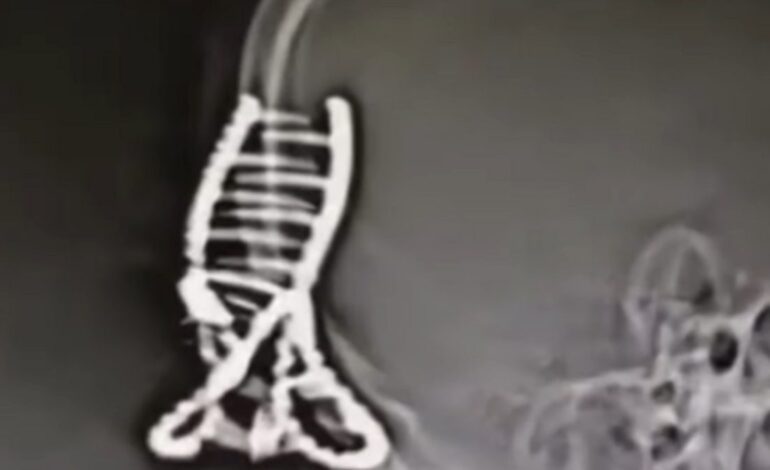

En uno de sus vídeos, el doctor Sri Manivannan el queria advertir Los riesgos de usar una pinza para el cabello. en la cabeza en caso de accidente de tráfico. Son un objeto muy común y práctico, ya que te permiten recoger todo tu cabello sin esfuerzo. Sin embargo, dentro del coche Es mejor quitárselo.

En efecto, una joven del Reino Unido Ella contó la historia de cómo una simple pinza para el cabello casi le cuesta la vida. Después de sufrir un accidente automovilístico debido a una niebla muy intensa, los médicos que la atendieron en el hospital comprobaron que, debido a este accesorio para el cabello, Sufrió un corte de 30 cm desde la ceja izquierda hasta la nuca.

“Quiero aconsejar a la gente quita las pinzas de tu cabello antes de conducir, porque tengo miedo de que le pueda pasar a otra persona. «He tenido mucha suerte, pero no quiero que nadie más corra el riesgo», añadió.